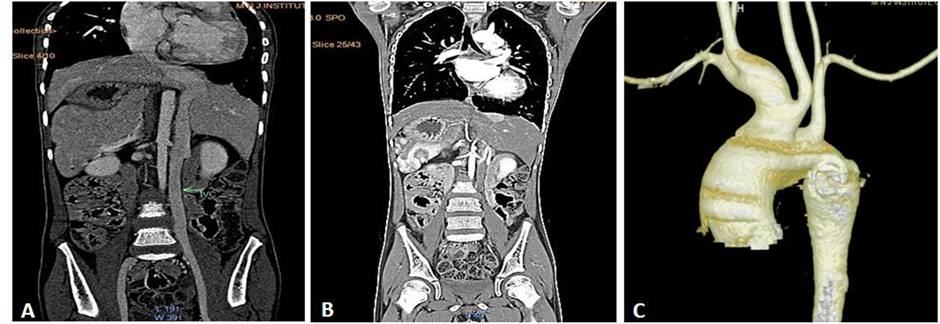

Computed tomography (CT) of chest and CT angiography also indicated isolated levocardia with SI along with anomalous course of IVC (lie to the left of aorta and entered right atrium after crossing aorta from left to right) (Figure 4(A) & Figure 4(B)) and bovine aortic arch (Figure 4(C)). However, other abnormalities were not found. We confirmed the diagnosis of isolated levocardia with SI, anomalous course of IVC, bovine aortic arch and PDA.

Figure 4. (A) & (B) Computed Tomography scan reconstructed film showing anomalous course of inferior vena cava which lie left side of aorta entering into right atrium crossing from left to right and abdominal situs inversus; (C) Computed Tomography Angiography showing bovine aortic arch.